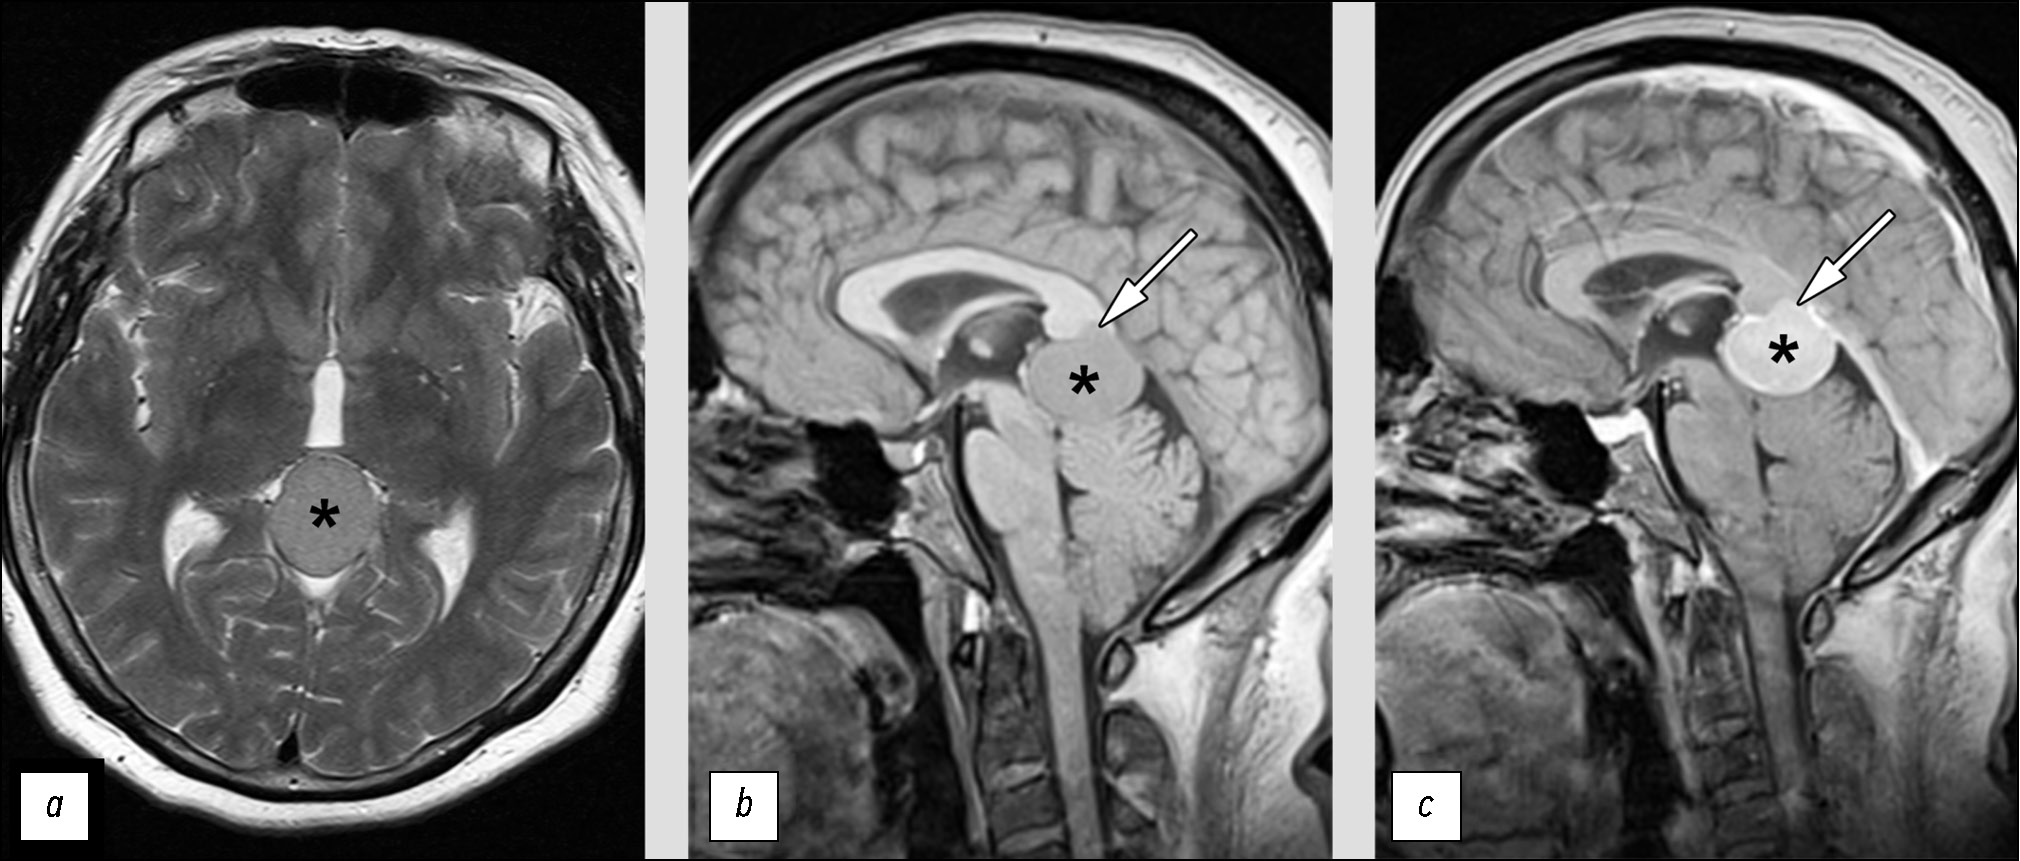

Инструментальная диагностика. На серии МРТ-изображений (рис. 5) в эпифизарной области визуализировано внемозговое образование однородной структуры и контрастирования, размерами 2,9×2,6×2,5 см. Опухоль деформирует пластинку четверохолмия, суживается просвет водопровода мозга без развития окклюзионной гидроцефалии.

Рис. 5. Нетипичные проявления злокачественной менингиомы на магнитно-резонансной томографии: a — Т2-ВИ; b — Т1-ВИ; c — Т1-CE. Представлена злокачественная менингиома (*), расположенная в эпифизарной области. Определяется инвазия опухоли в валик мозолистого тела (стрелка).

Граница между новообразованием и валиком мозолистого тела на небольшом протяжении не прослеживается, но отёка вещества мозга в данной области не определяется.

Дифференциальная диагностика. Однородная структура и гомогенное контрастирование послужили решающими факторами для ошибочного отнесения выявленного образования к доброкачественным менингиомам. Вероятно, из-за их наличия рентгенолог не обратил внимания на наличие небольшого участка инвазии опухоли в вещество мозга (валик мозолистого тела).

Лечение. Пациентке выполнена резекция опухоли, гистологическое заключение: атипичная (Grade 2) менингиома, С70.0 9539/32.